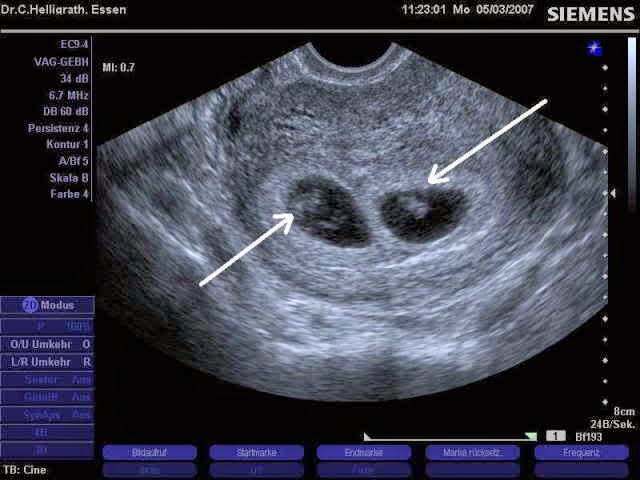

Frühgeburt: Ab wann ein Baby lebensfähig ist | kidsgo

Frühgeburt

Frühgeborene – An den Grenzen des Lebens